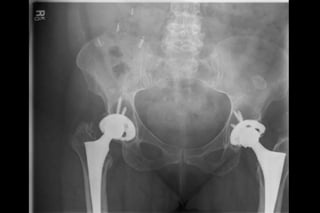

AP Pelvis

Workup

• Plain xrays

– Hip

»AP pelvis

»AP/Lateral hip

»Not typically weight bearing